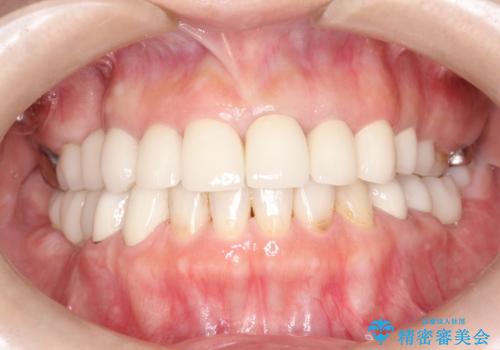

セラミックと矯正を併用してきれいな前歯へ

- 全体的な治療と、見た目をきれいにしたとのご希望で来院されました。

上顎の前歯はガタガタがあり、過去に治療した歯はつぎはぎのようになっており、審美的に周囲と調和がとれていない状態でした。

今回矯正治療で歯並びを整えた後に、セラミックを装着することにより、審美的・機能的に優れた仕上がりにすることができました。